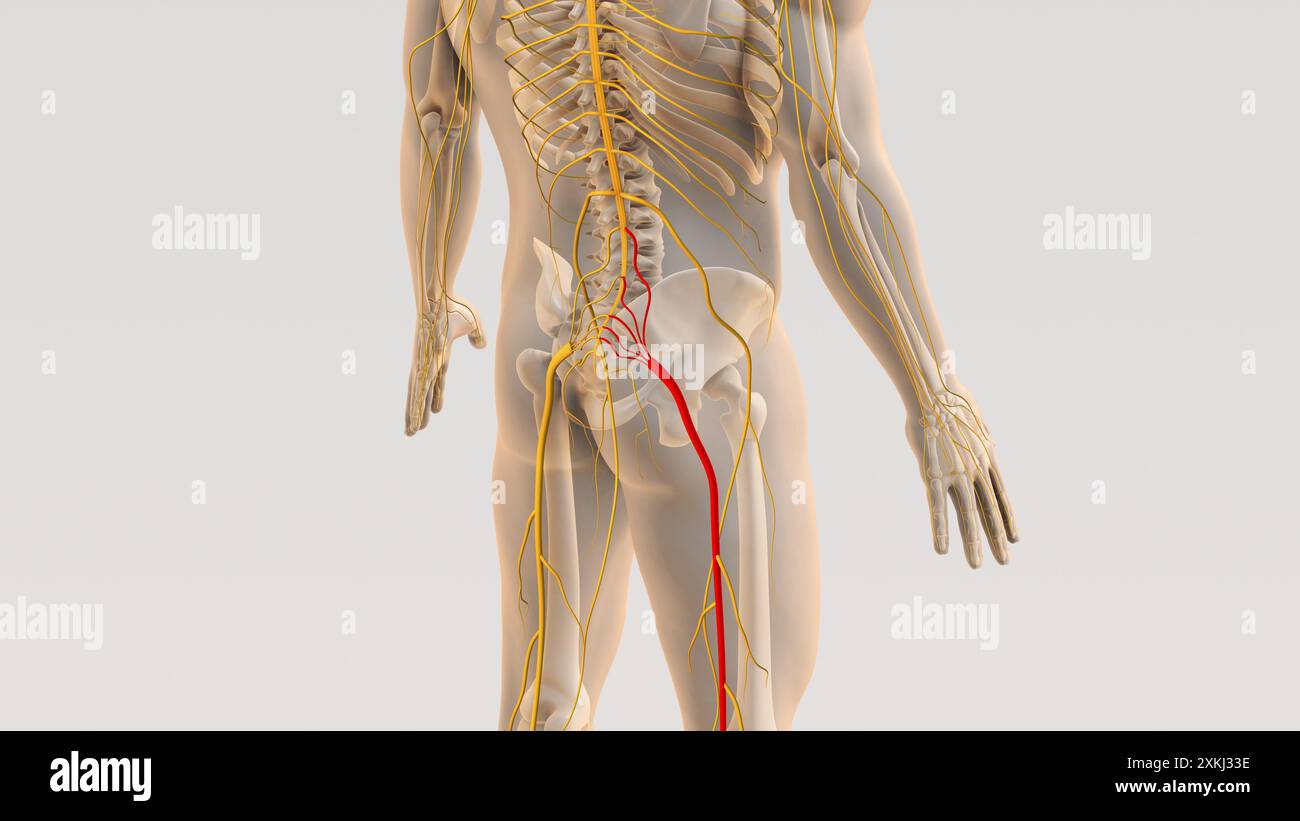

Medizinisches Konzept für Ischiasnervenbeschwerden Stockfotohttps://www.alamy.de/image-license-details/?v=1https://www.alamy.de/medizinisches-konzept-fur-ischiasnervenbeschwerden-image614438920.html

Medizinisches Konzept für Ischiasnervenbeschwerden Stockfotohttps://www.alamy.de/image-license-details/?v=1https://www.alamy.de/medizinisches-konzept-fur-ischiasnervenbeschwerden-image614438920.htmlRF2XKJ334–Medizinisches Konzept für Ischiasnervenbeschwerden

Ischiaswirbelsäule und Nervenschmerz medizinisches Konzept Stockfotohttps://www.alamy.de/image-license-details/?v=1https://www.alamy.de/ischiaswirbelsaule-und-nervenschmerz-medizinisches-konzept-image614438930.html

Ischiaswirbelsäule und Nervenschmerz medizinisches Konzept Stockfotohttps://www.alamy.de/image-license-details/?v=1https://www.alamy.de/ischiaswirbelsaule-und-nervenschmerz-medizinisches-konzept-image614438930.htmlRF2XKJ33E–Ischiaswirbelsäule und Nervenschmerz medizinisches Konzept